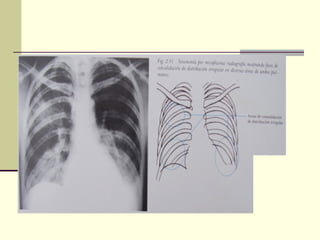

Evidencia Pulmonar

 Inicia infiltración pulmonar temprana en

forma dispersa e irregular, a menudo es más

extensa en los radiografías que indican los

signos clínicos. Puede avanzar de un lóbulo a

otro y ser bilateral